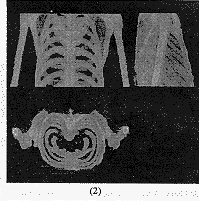

采用本文介绍的直接体绘制算法,对预处理过的医学图像数据集进行三维重建,发现效果良好。如图3所示,为采用该方法进行三维重建的结果,由于使用了硬件加速功能,因而达到了较高的重建速度。其中:

(1)由人体胸腔CT图像序列中提取出的120×220×170的骨骼数据集三维重建图,非透明度取值为0.8;

(2)由人体胸腔CT图像序列中提取出的120×220×170的骨骼数据集三维重建三视图,非透明度取值为0.5;